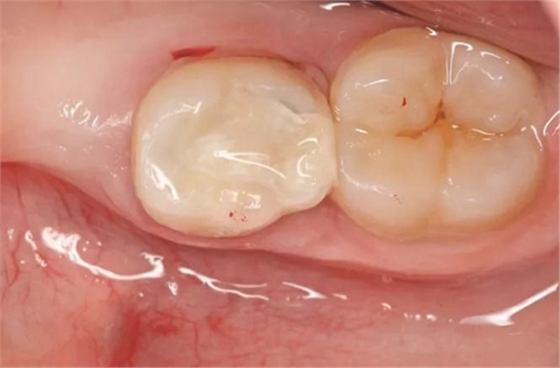

玻璃離子水門?。℅IZ)基于其易操作性而廣泛地被兒童牙科使用。對牙體組織的化學(xué)粘附、低熱膨脹和生物相容性被認(rèn)為是這種充填材料的優(yōu)點(diǎn)。傳統(tǒng)GIZ的主要缺點(diǎn)是其對濕度和干燥的耐受性較差。充填之后可以通過使用粘合劑或GIZ漆覆蓋來規(guī)避這些問題。其他弱點(diǎn)還有低耐磨性和低彎曲強(qiáng)度,這可能會導(dǎo)致邊緣缺損和峽部斷裂(特別是II 類洞充填)(圖2)。II類洞玻璃離子充填的平均存留時間僅為1.4至2年,這一年限明顯低于其他充填材料(如銀汞合金、復(fù)合體或復(fù)合樹脂)。

圖2:玻璃離子填充物在洞的園中峽部斷裂,部分填充材料脫落